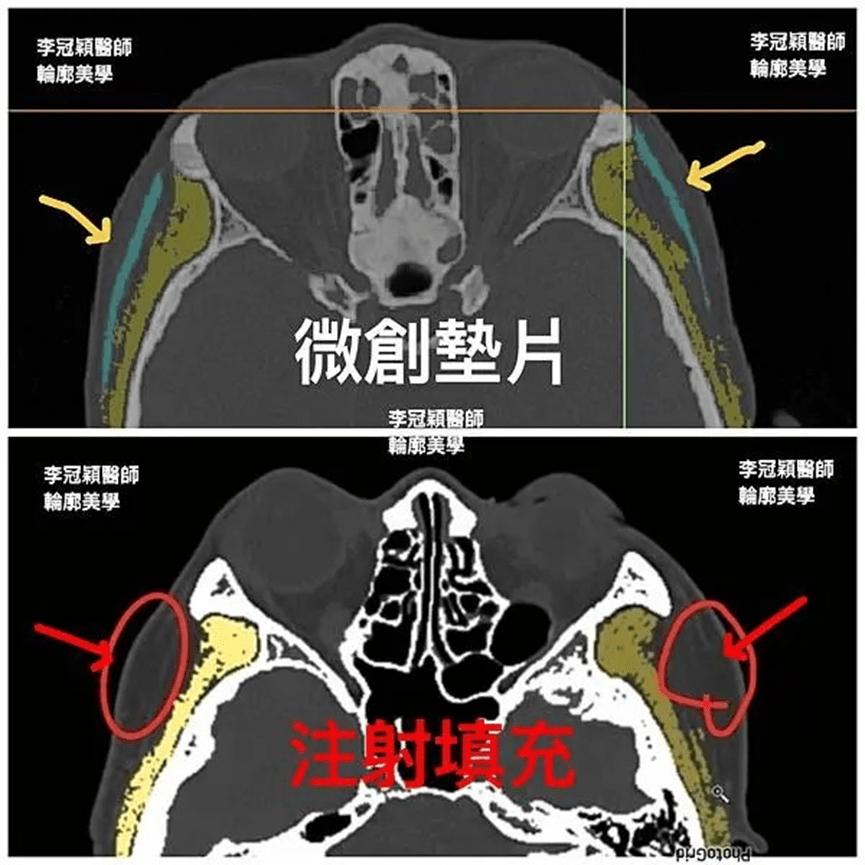

電腦斷層發現:下圖為墊片位置穩定平順(紅色箭頭),下下圖紅圈處為注射脂肪下移與吸收不均的腫塊。為李醫師客製化墊片手術後兩年半長期和太陽穴注射填充結果比較:

Filler/ fat augmentation is quite different from the implant sheet on temple area. Long term results show on 3D CT scan, we can find the filled temple disfigured a lot compared with the implant sheet on temple contour.

範例 二:淺藍色為墊片(黃色為肌肉部分)

上圖:在3D電腦斷層掃描顯像:微創墊片在太陽穴(近三年)和注射填充的效果對比

紅色箭頭腫塊為填充物。容易形成饅化大頭感。